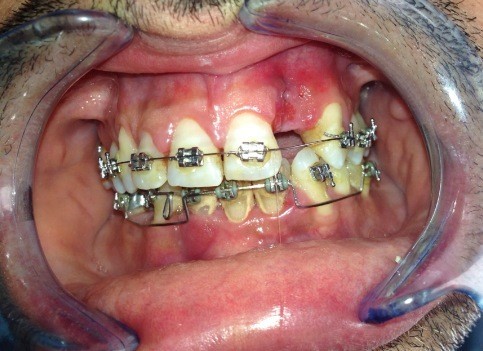

rigenerazione grave difetto parodontale a carico una intera emiarcata